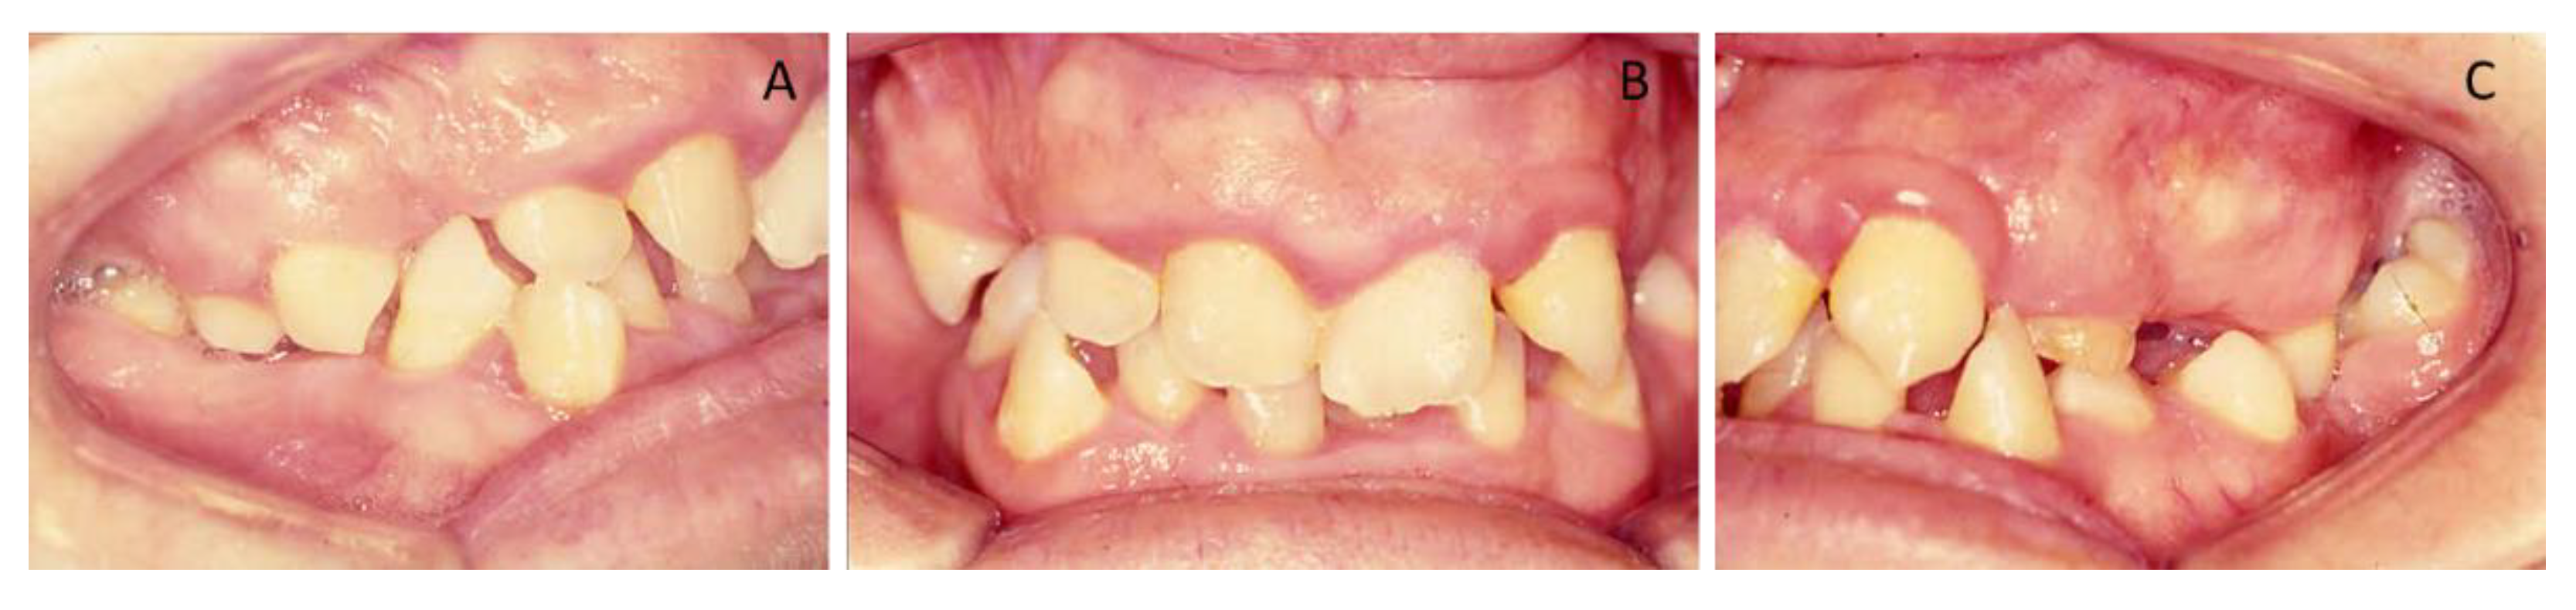

Figure 9. Post-treatment intra-oral photographs (AC). At four years and six months, they showed a stable occlusion with orthodontic treatment, orthognathic surgery, and oral rehabilitation.